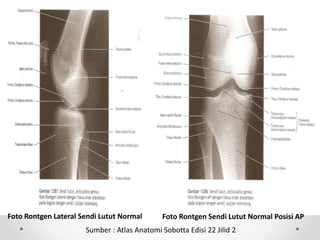

Foto Rontgen Lateral Sendi Lutut Normal Foto Rontgen Sendi Lutut Normal Posisi AP

Sumber : Atlas Anatomi Sobotta Edisi 22 Jilid 2